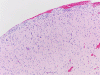

Pathology of the Case: On MRI, there is an infiltrative non-enhancing lesion that dominates the right frontal lobe but extends across the genu of the corpus callosum into the left frontal region, and extends posteriorly to the right basal ganglia region, subinsular region, and anterior right temporal lobe on his pre-operative MRI. On intra-operative consultation cytologic prepartion (Panel A), there is a rather monotonous population of cells with hyperchromatic nuclei and elongated cytoplasmic processes (arrow in Panel A) reminiscent of dripping syrup or honey and that these processes form a fine meshwork. This is a strong suggestion of glioma. Such cytoplasmic processes can be seen in astorcytomas, oligodendrogliomas, and ependymomas. On frozen section (Panel B), the tumor is rather hypocellular. However, there seems to be two sizes of nuclei present. The first are large, hyperchromatic, with elongated morphology reminscent of a baking potato. The second is a much smaller one most consistent with that of a non-neoplastic glial cells. These features indicate an infiltration of atypical neoplastic glial cells in a background of non-neoplastic cells. This is a diffuse glioma until otherwise proved.

The some parts of the permanent sections (Panel C and D), there is higher cellularity in comparison to the frozen section. One should note that the cellularity of the tumor did not change. Freezing the tissue generates many large ice crystals and gives the bubbly or spongiotic appearance of glioma on frozen section (Panel B). During formalin fixation, the tumor shrink. With the same number of nuclei present, the permanent section always look more cellular than the frozen section in glioma. Also, the large bubbly look now becomes fine spongiotic change.